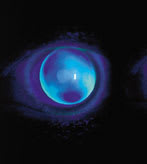

Case Example 1. A 15-year-old female sustained a penetrating injury OS that required cataract extraction. I fit her with a large keratoconic lens design (Nicone #2) in aphakic power. Figure 5 reveals the massive sutured scar. Figure 6 shows the fluorescein pattern.

| Figure 5. Penetrating injury with aphakic contact lens in place. Note the large scar of the sutured cornea. |

Figure 6. Fluorescein pattern of a lens fit on the cornea shown in Figure 5.